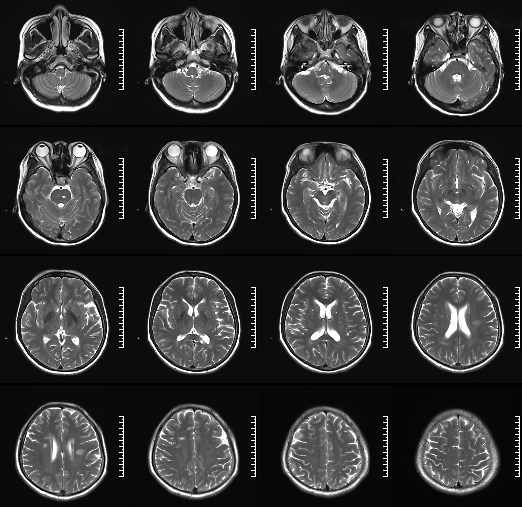

术前影像

HRMRI

左侧脑室旁亚急性期-慢性期脑梗死